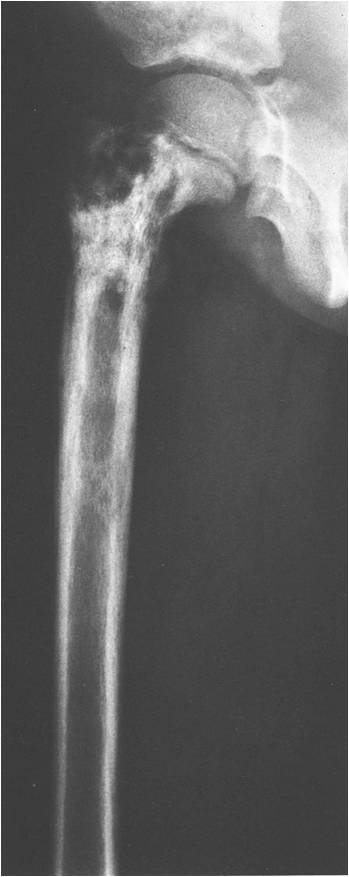

- Permeative or moth eaten bone destruction (55%)

- Geographic (11%); Blow out (1%); Blastic (2%); Normal XR (5%)

- Metadiaphysis (75%)

- Periosteal reaction—may look benign

Permeative Lesion

Permeative/Moth eaten lesion Reactive sclerosis (mixed lysis and sclerosis) Slight periosteal reaction